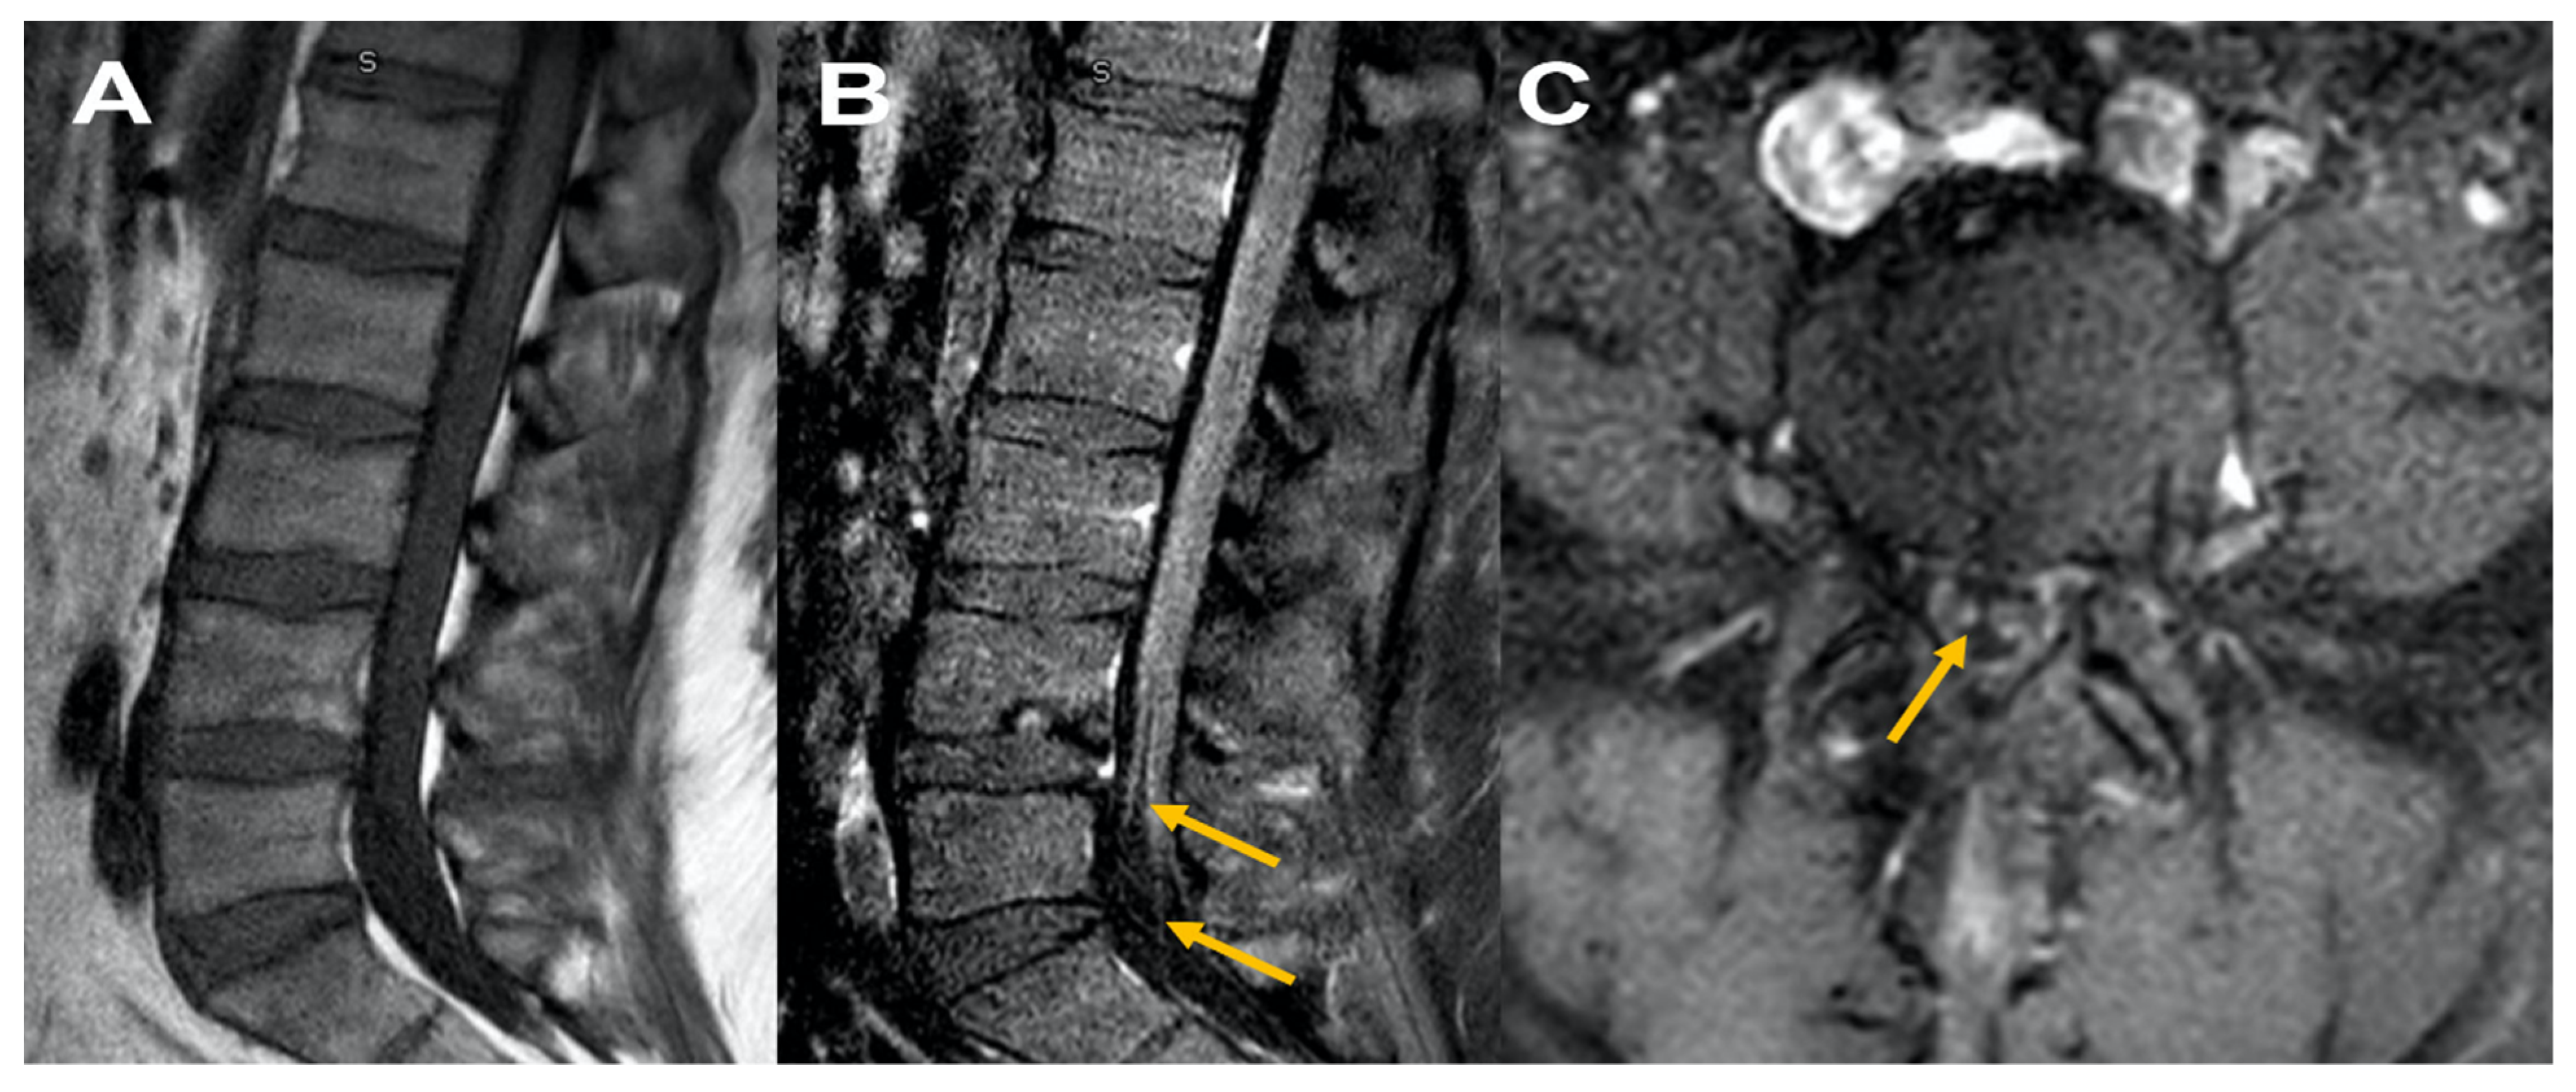

| Waheed et al./US [14] | 82 years/F | Pfizer | 14 days | GBS | Generalized malaise, body aches and difficulty walking | Showed albumino-cytologic dissociation Protein of 88 mg/dL, Cell Count: WBC of 4/mm3 | MRI L spine: Enhancement of cauda equina nerve roots | Normal | N/A | N/A | IVIG | Recovered |

| Razok et al./Qatar [15] | 73 years/M | Pfizer | 20 days | GBS | Progressive lower limb weakness | Protein: 80 mg/dL (elevated) Cell Count: Normal Glucose: Normal Oligoclonal band: negative | MRI L spine: bilateral nerve root enhancement in the lumbar region and the upper part of the cauda equina | Normal | N/A | N/A | IVIG | Recovered |

| Prasad et al./US [20] | 41 years/M | Janssen | 21 days | GBS/BFP variant | Difficulty feeding and ambulating | Cell count: 50/mm3 Protein: 562 mg/dL Glucose: 67 mg/dL | MRI L spine with contrast showed thickening of cauda equina nerve roots | N/A | N/A | N/A | IVIG | Recovered |

| Márquez Loza AM et al./US [16] | 60 years/M | Janssen | 10 days | GBS | Pain in her back and leg. Nausea, vomiting, headache and diplopia | CSF Protein: 140 mg/dL, Cell count: 9 nucleated cells/mm3 Glucose: Normal | MRI L spine: demonstrated enhancement of the cauda equina | N/A | N/A | N/A | IVIG | Recovered |

| Patel et al./UK [17] | 37 years/M | AstraZeneca | 14 days | GBS | Persistent back pain, distal paraesthesia in hands and feet, symmetrical progressive ascending muscle weakness | CSF protein:177 mg/dL Glucose: 70 mg/dL Cell Count: < 1/mm3 | MRI L spine: illustrated globally thickened cauda equina nerve root particularly at the level of S1 | N/A | N/A | N/A | IVIG | Improved |